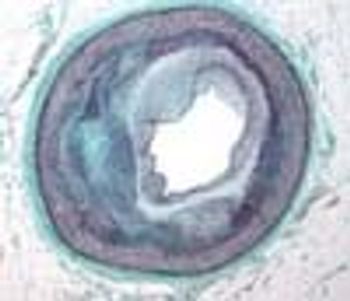

A tip for identifying pinworm infections in pediatric patients.